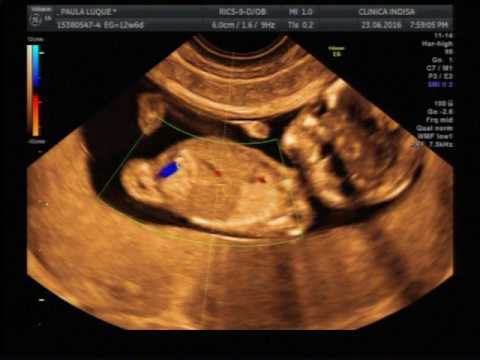

Ya tienes 12 semanas hija mia, y nuestras suposiciones se hicieron realidad (en un 90% al menos, pero eso ya es casi seguro), y tal como dice la canción, ya vienes mi Magdalena amada, y vienes muy inquieta, por lo que nos dijo el doctor ¡¡¡que inquieta tu hija!!!!! (primera acusación de desordenada, seguirás los pasos de tu padre y pasaré citado en el colegio??? De ser así estaré orgulloso, mientras tengas claras tus prioridades)

Lo mas importante es que vienes bien, sanita, fuerte e inquieta, deseosa de seguir creciendo y desarrollándote dentro de la guatita de tu mamá.

La ecografía muestra como tus piernas, brazos y tus pequeños órganos ya están en pleno proceso de formación, al igual que tu columna y arterias, las cuales tanto nos costó ver. Tu nariz viene sin problemas, y tus latidos siguen firmes  a 157 por minuto.